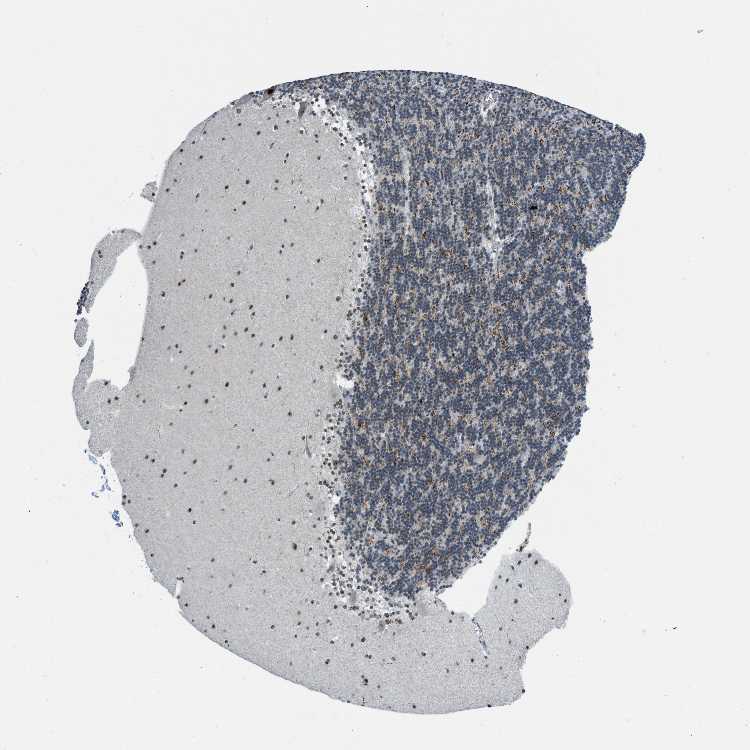

CEREBELLUM - Antibody stainingi

Antibody staining in the annotated cell types in the current human tissue is reported as not detected, low, medium, or high, based on conventional immunohistochemistry profiling in selected tissues. This score is based on the combination of the staining intensity and fraction of stained cells.

Each image is clickable and will lead to virtual microscopy that enables deeper exploration of all samples and also displays staining intensity scores, fraction scores and subcellular localization as well as patient and tissue information for each sample.

Antibody HPA018334

Purkinje cells High

Cells in granular layer Low

Cells in molecular layer Medium